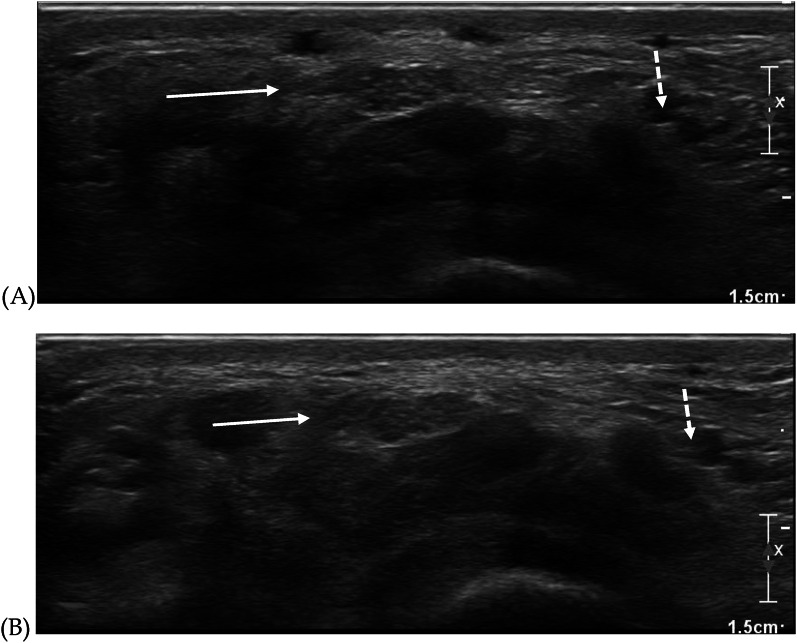

Abstract Image